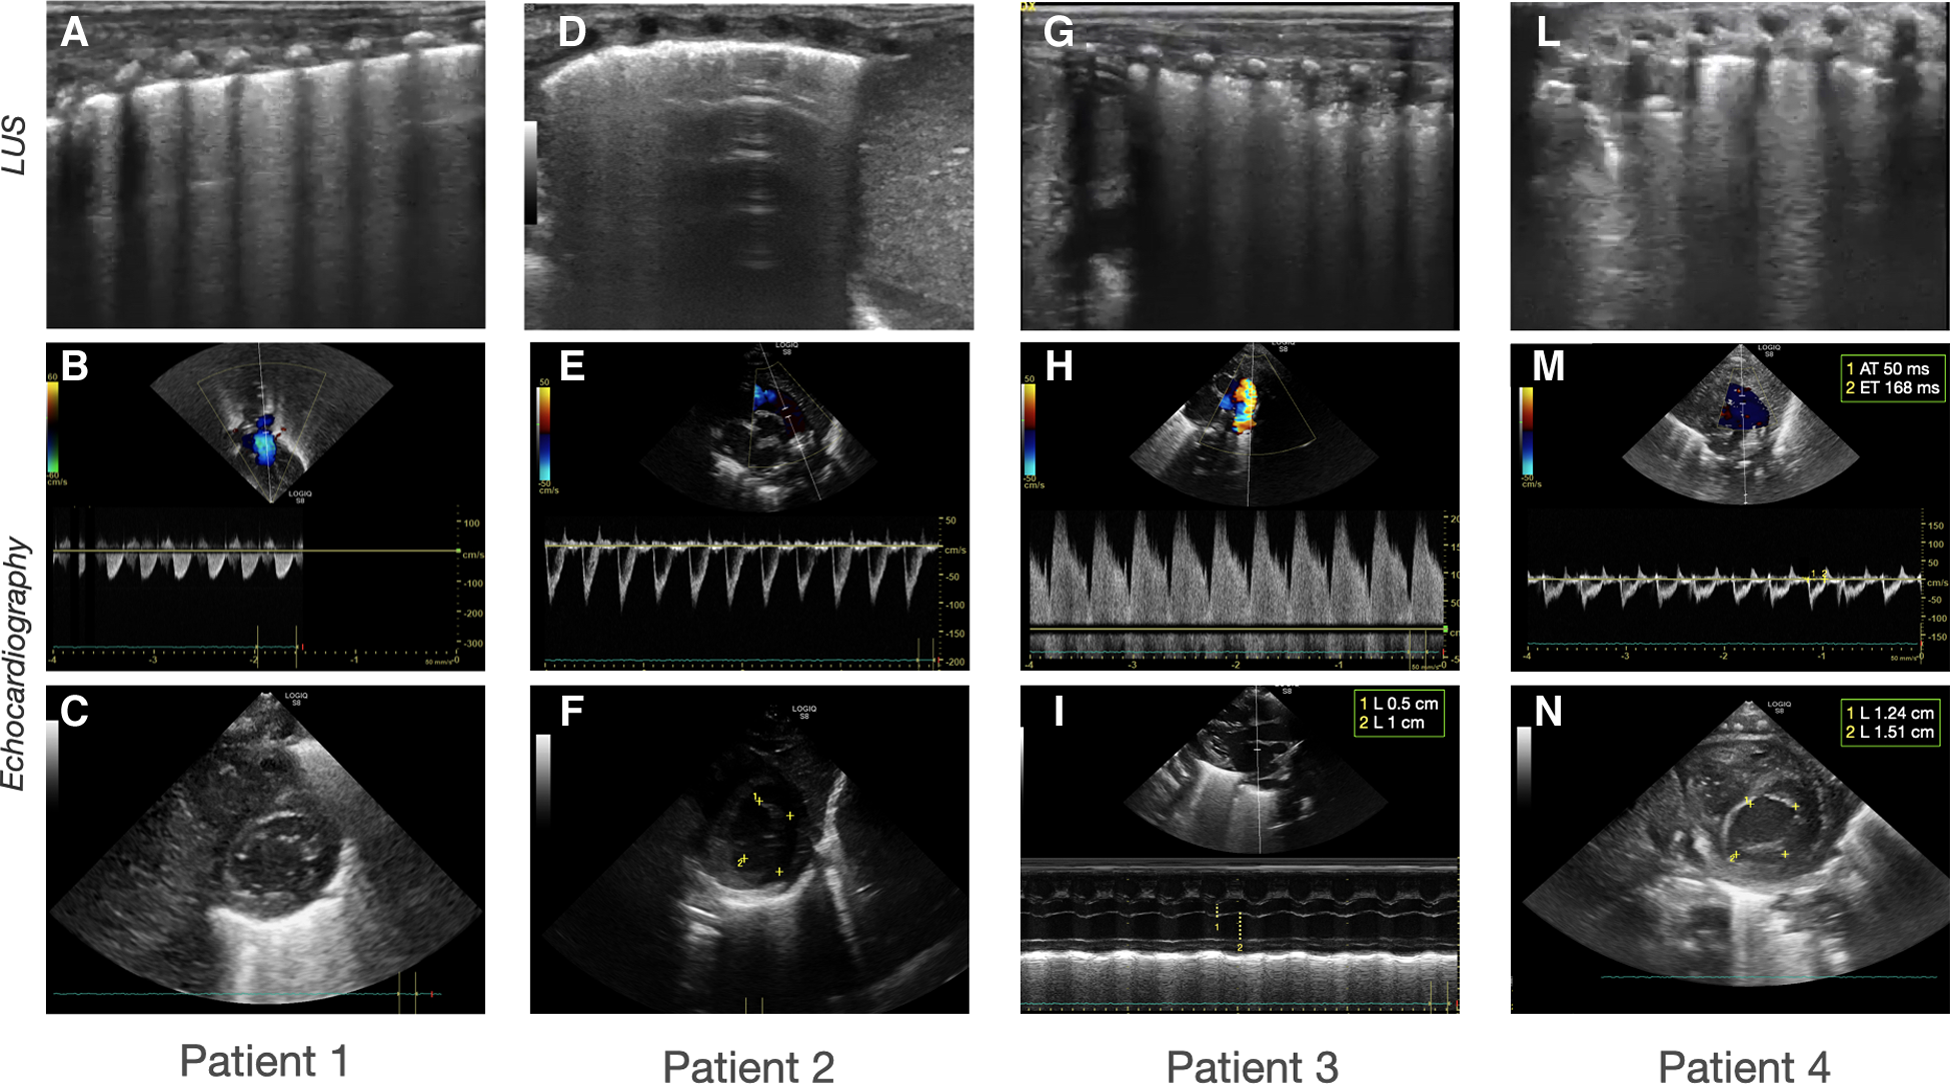

Sonographic patterns of bronchodysplasia (BPD). Representative pictures of Lung Ultrasound (LUS) and echocardiography of the patients at the time of the beginning of therapy. (A–C) Case 1: (A) LUS showing homogenously and gravity-related distributed B-lines with a normal pleural line; (B) color-Doppler of the pulmonary artery showing normal flow; (C) B-mode evaluation of ventricular chambers showing normal eccentricity index (EI). (D-F) Case 2: (D) LUS showing inhomogeneous B-line distribution with spared areas of normal sonographic lung appearance, surrounded by areas containing multiple B-lines. Pleural line thickened and irregular; (E) color-Doppler of the pulmonary artery showing normal flow; (F) B-mode evaluation of ventricular chambers showing normal EI. (G-I) Case 3: (G) LUS homogenously and gravity-related distributed B-lines with subpleural atelectasis of the dependent regions; (H) color-Doppler of the patent ductus arteriosus showing pulsatile flow; (I) M-mode evaluation of the left atrium (LA) to aorta (Ao) ratio, showing important dilation of the ratio atrium (LA:Ao = 2); (L-N) Case 4: (L) LUS showing confluent B-lines with sparing areas, thickened pleural line, and with subpleural atelectasis; (M) color-Doppler of the pulmonary artery showing decreased acceleration time/ejection time (AT/ET) = 0.28; (N) B-mode evaluation of ventricular chambers showing decreased EI (EI = 1.2).

In our report, we borrowed these concepts from adult medicine, employing LUS to distinguish the different interstitial phenotypes of BPD, showing a consistent response to targeted treatment. Patients 1 and 3 were classified as congestive LUS pattern, given the regular gravity-dependent distribution of B-lines. This was confirmed by repeating LUS examination after the position change. The use of TnEcho allowed us to differentiate the etiology of pulmonary edema. Differently from Patients 1 and 3, LUS showed multiple diffuse B-lines with irregular distribution non-gravity-dependent in both the anterior and posterior lung fields of Patient 2. Furthermore, the pleural line appeared thickened, coarse, and irregular. Taken together, these findings suggested an interstitial disorder related to fibrosis/inflammation rather than pulmonary congestion.